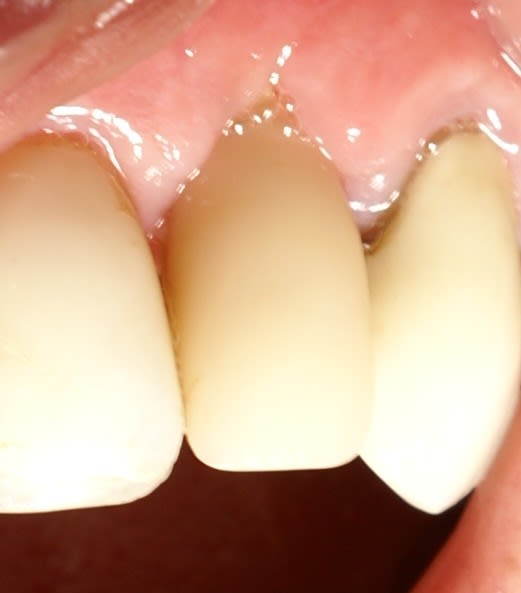

Ce cas est limite et aurait pu être traité en deux temps mais bon, j'ai opté pour y aller franco...

La seamine prochaine je vous montrerai la finition céramique.